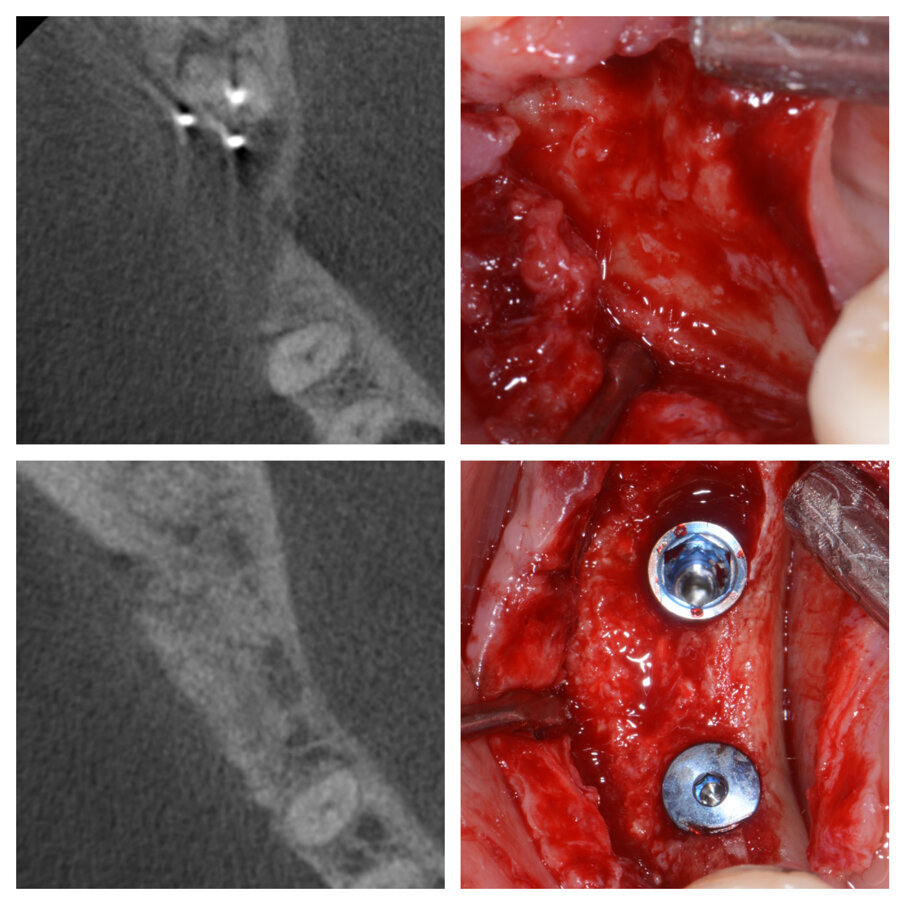

Fig. 1a_Estrazione di radice distale di 46 e innesto su deficit di 45 e 46.

Fig. 1d_Tessuti duri prima e dopo la tecnica S.A.T., posizionamento implantare.

La tecnica è indicata per elementi dentali da estrarre mesio inclinati o elementi di ponte, che presentino un deficit orizzontale della cresta ossea a fianco dell’elemento da estrarre. Il protocollo operativo prevede, dopo l’estrazione, una incisione in cresta fino al dente contiguo e intrasulculare per mezzo dente sia vestibolare che buccale-palatale, se necessario. Si procede poi scollando ed evidenziando la parte ossea dove dovremo posizionare la membrana e il biomateriale, senza eccedere poiché lo scollamento minimo ci garantirà la stabilità dell’innesto. Raggiunte le pareti che riprendono uno spessore osseo morfologicamente normale si interrompe lo scollamento e si imbusta una membrana in collagene precedentemente tagliata e bagnata con la colla di fibrina, in modo che si incolli al lembo vestibolare. A questo punto il biomaterale miscelato con la colla di fibrina (Sticky Bone) viene imbustato poco per volta iniziando dall’alveolo e poi all’interno del sito creato dallo scollamento, senza necessità di fori nella corticale (Figg. 2a, 3a, 4a, 5, 6a). La rigenerazione viene guidata dai tessuti che ci indicheranno quanto materiale poter inserire, non effettuando scarichi verticali è il lembo stesso a essere contenitivo e a dare stabilità all’innesto. Il lembo viene suturato a punti staccati singoli ottenendo una chiusura per prima intenzione senza dover incidere il periostio (Figg. 1a, 2a, 3a, 6a); mentre nella zona dell’alveolo, in cui gli strati di membrana possono essere aumentati, la sutura sarà incrociata e la guarigione per seconda intenzione. Ovviamente se dovessimo trovarci in difficoltà potremo creare un rilascio periostale, ponendo sempre attenzione a non far venire meno quella capacità contenitiva del lembo che è alla base di questa tecnica. Nei casi presentati il rilascio periostale non è stato eseguito, iniziare il lembo con un incisione bisellata in cresta può essere d’aiuto a evitare il rilascio periostale (Fig. 2a).

Tutti gli interventi eseguiti con questa tecnica, nove in tutto, hanno portato alla risoluzione del deficit orizzontale presente al momento dell’estrazione, e hanno permesso in tutte le zone trattate un buon inserimento implantare senza la necessità di ulteriori tecniche di GBR (Figg. 1d, 3a, 3d, 6b). Gli interventi sono stati eseguiti sia in mandibola che nel mascellare superiore, trattando edentulie singole e multiple. Non eseguendo lembi di scarico e scollando il meno possibile, i pazienti nei giorni successivi non presentano particolare gonfiore; anche il dolore è molto limitato e gestibile con poche dosi di antidolorifico per via orale, oltre la terapia antibiotica con Amoxicillina 875 mg. e Acido Clavulanico 125 mg. ogni 12 ore per sei giorni. Il primo caso risale al gennaio 2011 ed abbiamo quindi un controllo a più di 4 anni dal posizionamento implantare (Fig. 7). La stabilità dei tessuti duri e molli è risultata buona, non avendo perso alcun impianto e soprattutto non avendo casi di perimucosite-perimplantite.